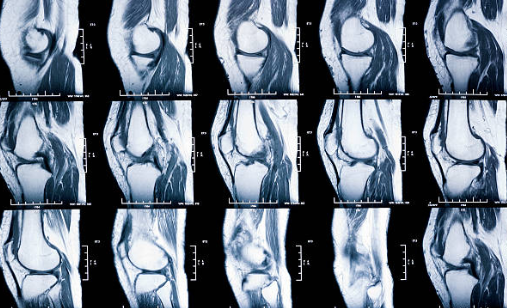

1. 무릎 연골 손상이란 무엇인지부터 쉽게 이해하기

무릎에는 뼈가 서로 부딪히지 않도록 도와주는 “연골”이 있어요.

대표적으로 두 가지가 중요합니다.

첫째, 관절연골

무릎뼈 끝을 매끈하게 감싸서 마찰을 줄여주고 충격을 흡수해요.

둘째, 반월상연골(반달연골)

무릎 안쪽과 바깥쪽에 있는 반달 모양의 연골로, 체중이 한쪽에 쏠리지 않도록 분산해 주는 역할을 해요.

이 연골이 닳거나 찢어지거나 손상되면 무릎이 뻣뻣하고 아프고, 걷는 자세까지 달라지면서 다른 관절까지 무리가 가기 쉬워요.

연골은 혈관이 거의 없어서 “피가 통하면서 빨리 낫는 조직”이 아니에요. 그래서 작은 손상도 그냥 넘기지 말고, 초기에 관리해 줘야 회복이 훨씬 수월합니다.